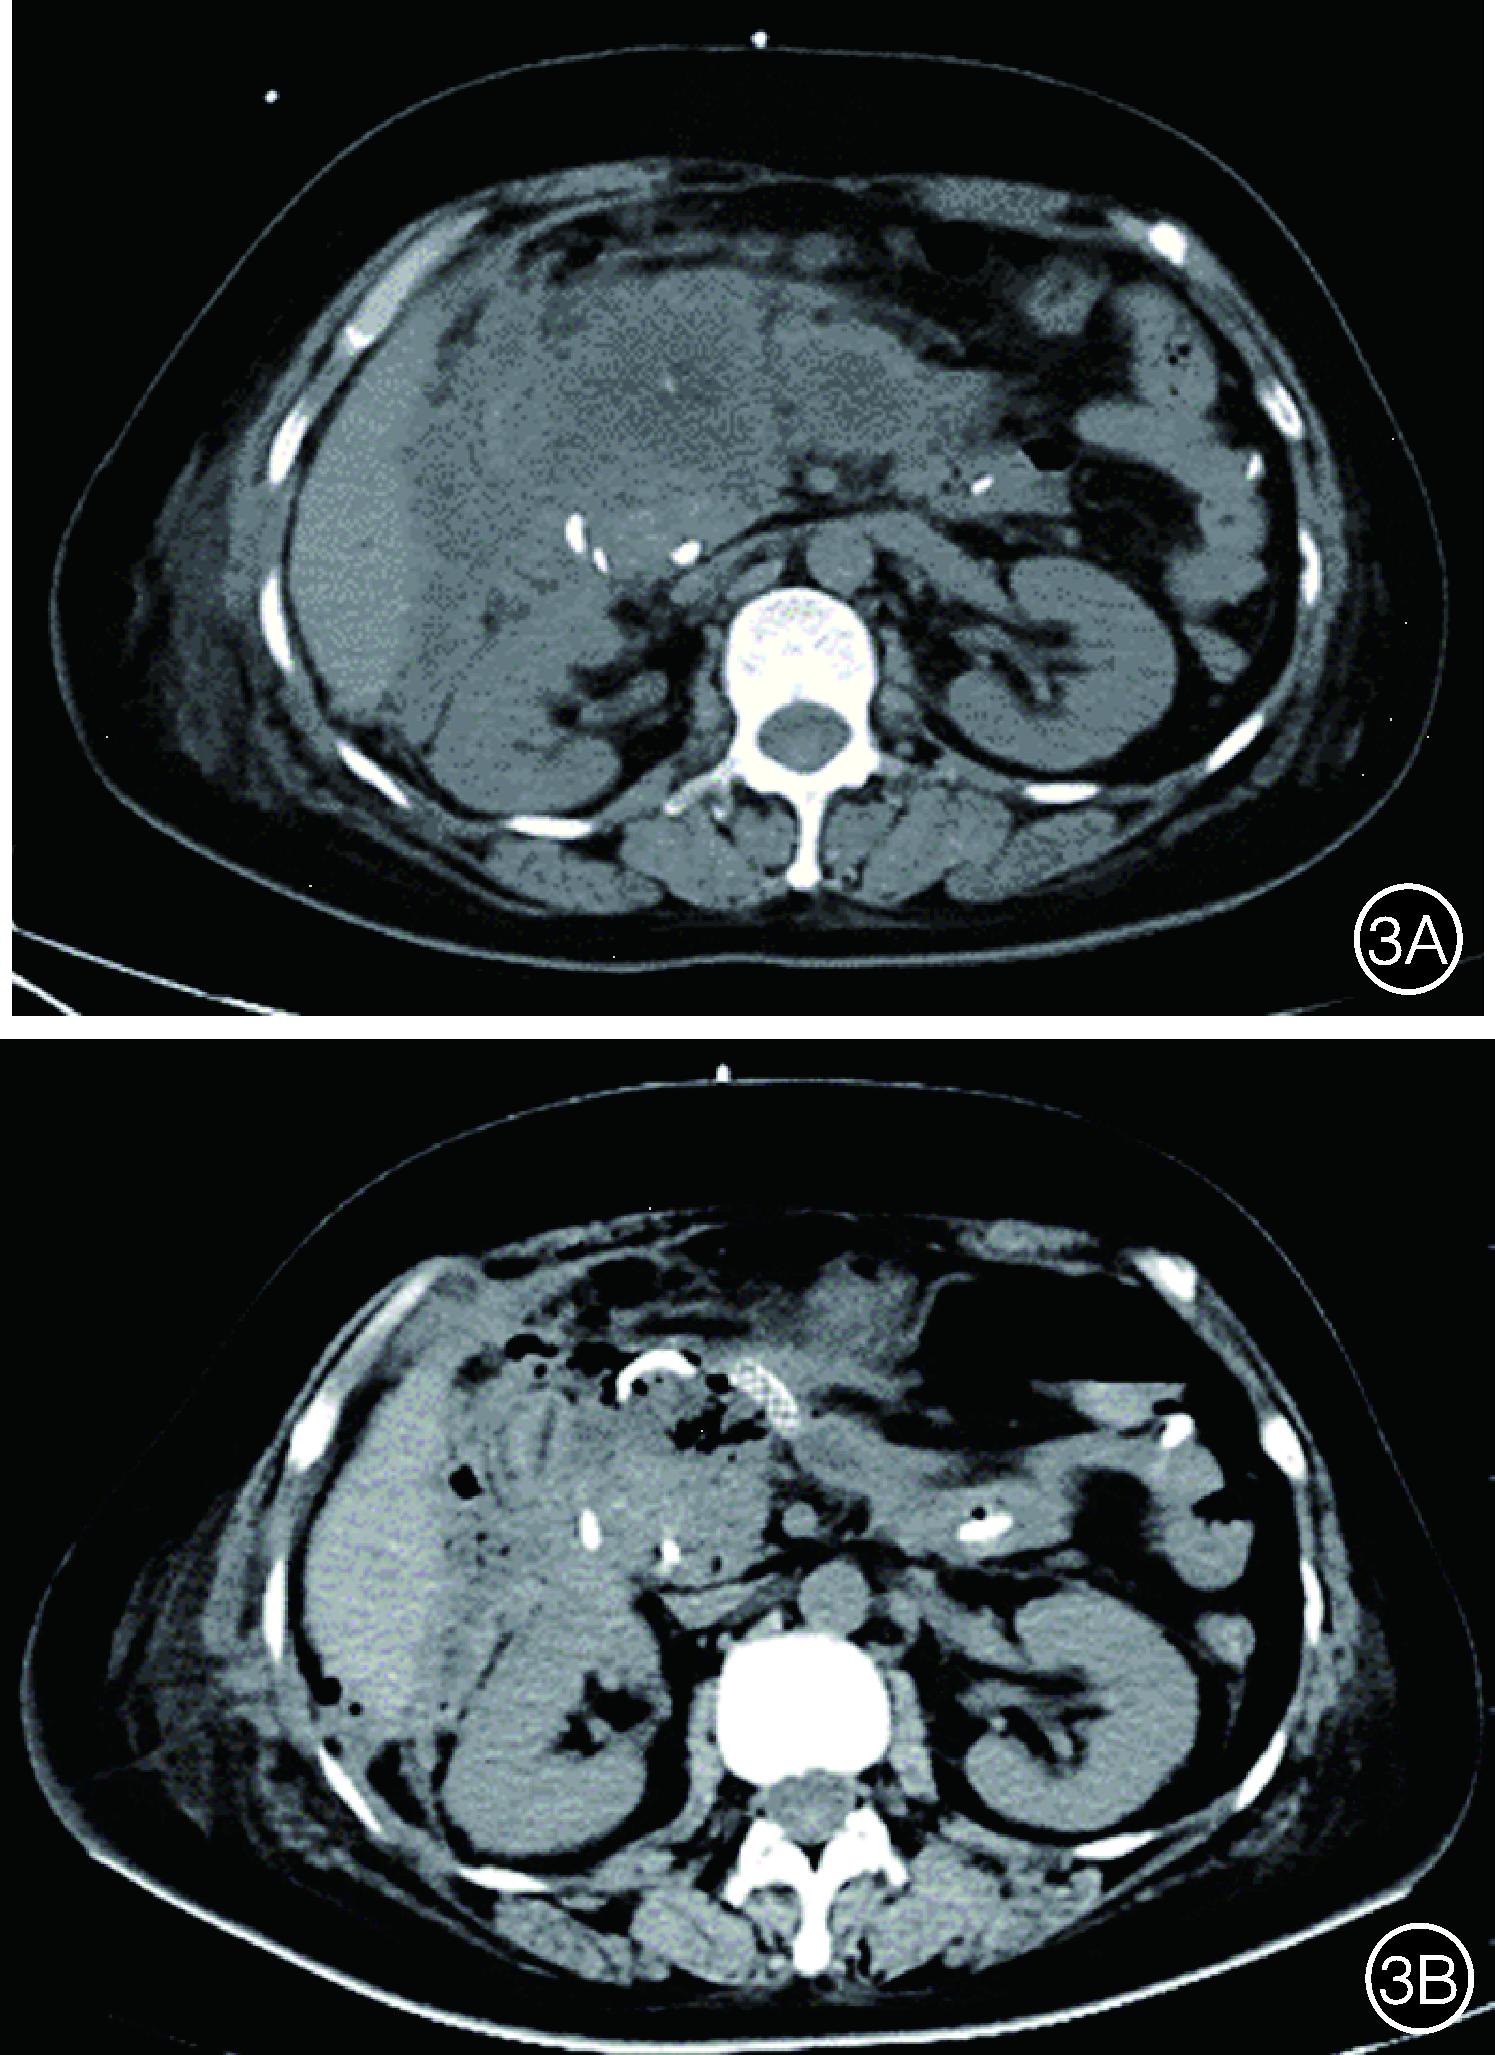

术后密切监测生命体征,动态复查血常规、生化、C反应蛋白及血淀粉酶、引流液淀粉酶以评估病情。根据病情需要择期复查腹部CT评估IPN吸收情况并制定下一步诊疗方案。对于经治疗后生命体征平稳且腹部CT检查见IPN较前明显吸收的患者,可择期安排出院,门诊定期复查(图3)。

图3 经胃联合经皮内镜治疗前后感染性胰腺坏死的影像学表现 3A:CT见治疗前感染性胰腺坏死面积大,累及胰腺及胰周; 3B:CT见治疗后感染性胰腺坏死基本完全吸收